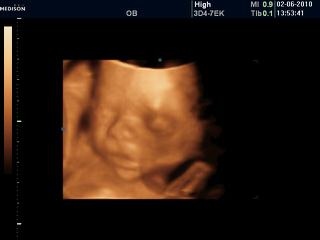

Nedočítala jsem, jedeme na 3D, tak dočtu později!

natalka tak pak přihod fotečku z 3D 🙂 . To s tím srdíčkem jsem nevěděla. Připadalo mi,že to kontrolovali dost důkladně. Tak snad bude všechno v pohodě,ted už to nedoženem,tak je to jedno. 🙂